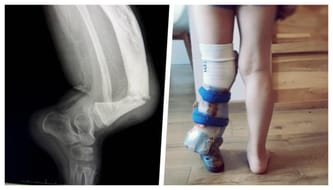

Nie mogliśmy się jednak załamać, musieliśmy dowiedzieć się jak najwięcej o dolegliwości synka. Gdy minął pierwszy szok, zaczęło się działanie. Bruno urodził się z wrodzoną wadą lewej kości piszczelowej, zdiagnozowaną jako miofibromatosis infantile. Jak się okazało - wada niezwykle rzadka, ale lekarze dawali nam nadzieję, że synek będzie chodził. Sądziliśmy, że w Polsce będzie najlepsza opieka, jednak wiele razy trafiliśmy na mur nie do przeskoczenia… Niestety, rzeczywistość w naszym kraju często jest brutalna - niewiele mówi się rodzicom, są zbywani, a na pytania o konkretne plany leczenia lub operacji lekarze odpowiadają wymijająco...

Mimo wszystkich przeciwności, nie ustawaliśmy w walce o sprawność naszego synka. Jednak gdy Bruno skończył 2,5 roku, jego nóżka się złamała… Nie upadł, nie uderzył w nic - kość pękła w wyniku przemęczenia! Synek zaczął płakać, że boli - bardziej niż zwykle. Pojechaliśmy do kliniki, w której leczyliśmy i ortezowaliśmy synka. Chcieliśmy usłyszeć dobre wieści, plan operacji, gotowość działania. Tymczasem spotkała nas brutalna rzeczywistość - wszystkie możliwości zachowawcze się wyczerpały…

Od maleńkiego Bruno nosi ortezy. Po wielu nieudanych próbach w kraju, zdecydowaliśmy się sprowadzać je z Niemiec - tam jakość i dopasowanie jest nieporównywalnie lepsze! Stare ortezy powodowały odparzenia, opuchnięcia, otarcia. Sprawiały ból, a to była dla nas zbyt wysoka cana... Kupujemy więc ortezy za granicą, bo tylko dzięki nim Bruno mógł chodzić! Jednak nawet one nie uchroniły nóżki od złamania. Jej stan pogarsza się w zastraszającym tempie - jeszcze we wrześniu była zgięta pod kątem 50 stopni, dziś to już 70! Wiem, że jeśli nic nie zrobimy, skutki mogą być opłakane…